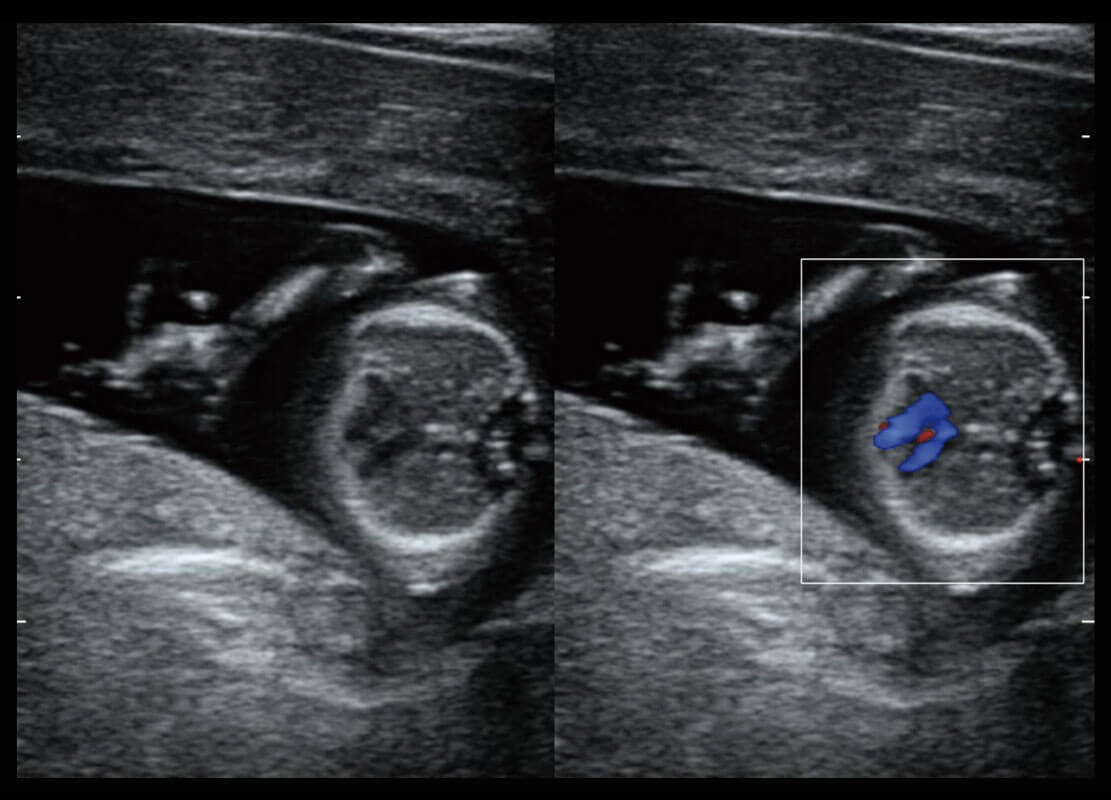

腔内妇科-卵巢

腔内三维-宫内节育器

早孕-胎心

高分辨率容积成像-早孕胎儿

光影成像-孕囊